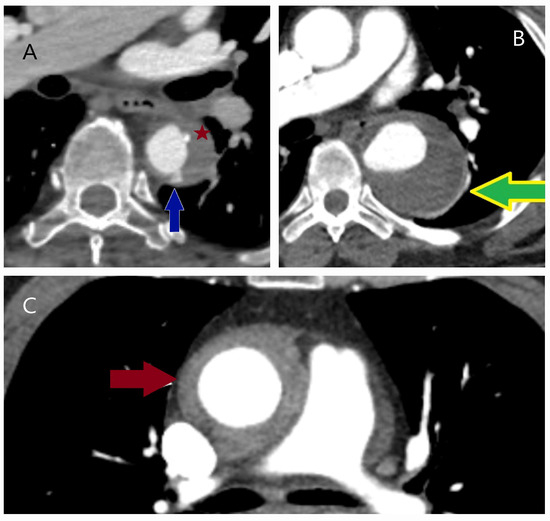

5.2.3. Computed Tomography

- Sathiadoss, P.; Haroon, M.; Wongwaisayawan, S.; Krishna, S.; Sheikh, A.M. Multidetector Computed Tomography in Traumatic and Nontraumatic Aortic Emergencies: Emphasis on Acute Aortic Syndromes. Can. Assoc. Radiol. J. 2020, 71, 322–334. [Google Scholar] [CrossRef] [PubMed]

- Ko, J.P.; Goldstein, J.M.; Latson, L.A., Jr.; Azour, L.; Gozansky, E.K.; Moore, W.; Patel, S.; Hutchinson, B. Chest CT angiography for acute aortic pathologic conditions: Pearls and pitfalls. Radiographics 2021, 41, 399–424. [Google Scholar] [CrossRef] [PubMed]

- Dreisbach, J.G.; Rodrigues, J.C.L.; Roditi, G. Emergency CT misdiagnosis in acute aortic syndrome. Br. J. Radiol. 2021, 94, 20201294. [Google Scholar] [CrossRef]